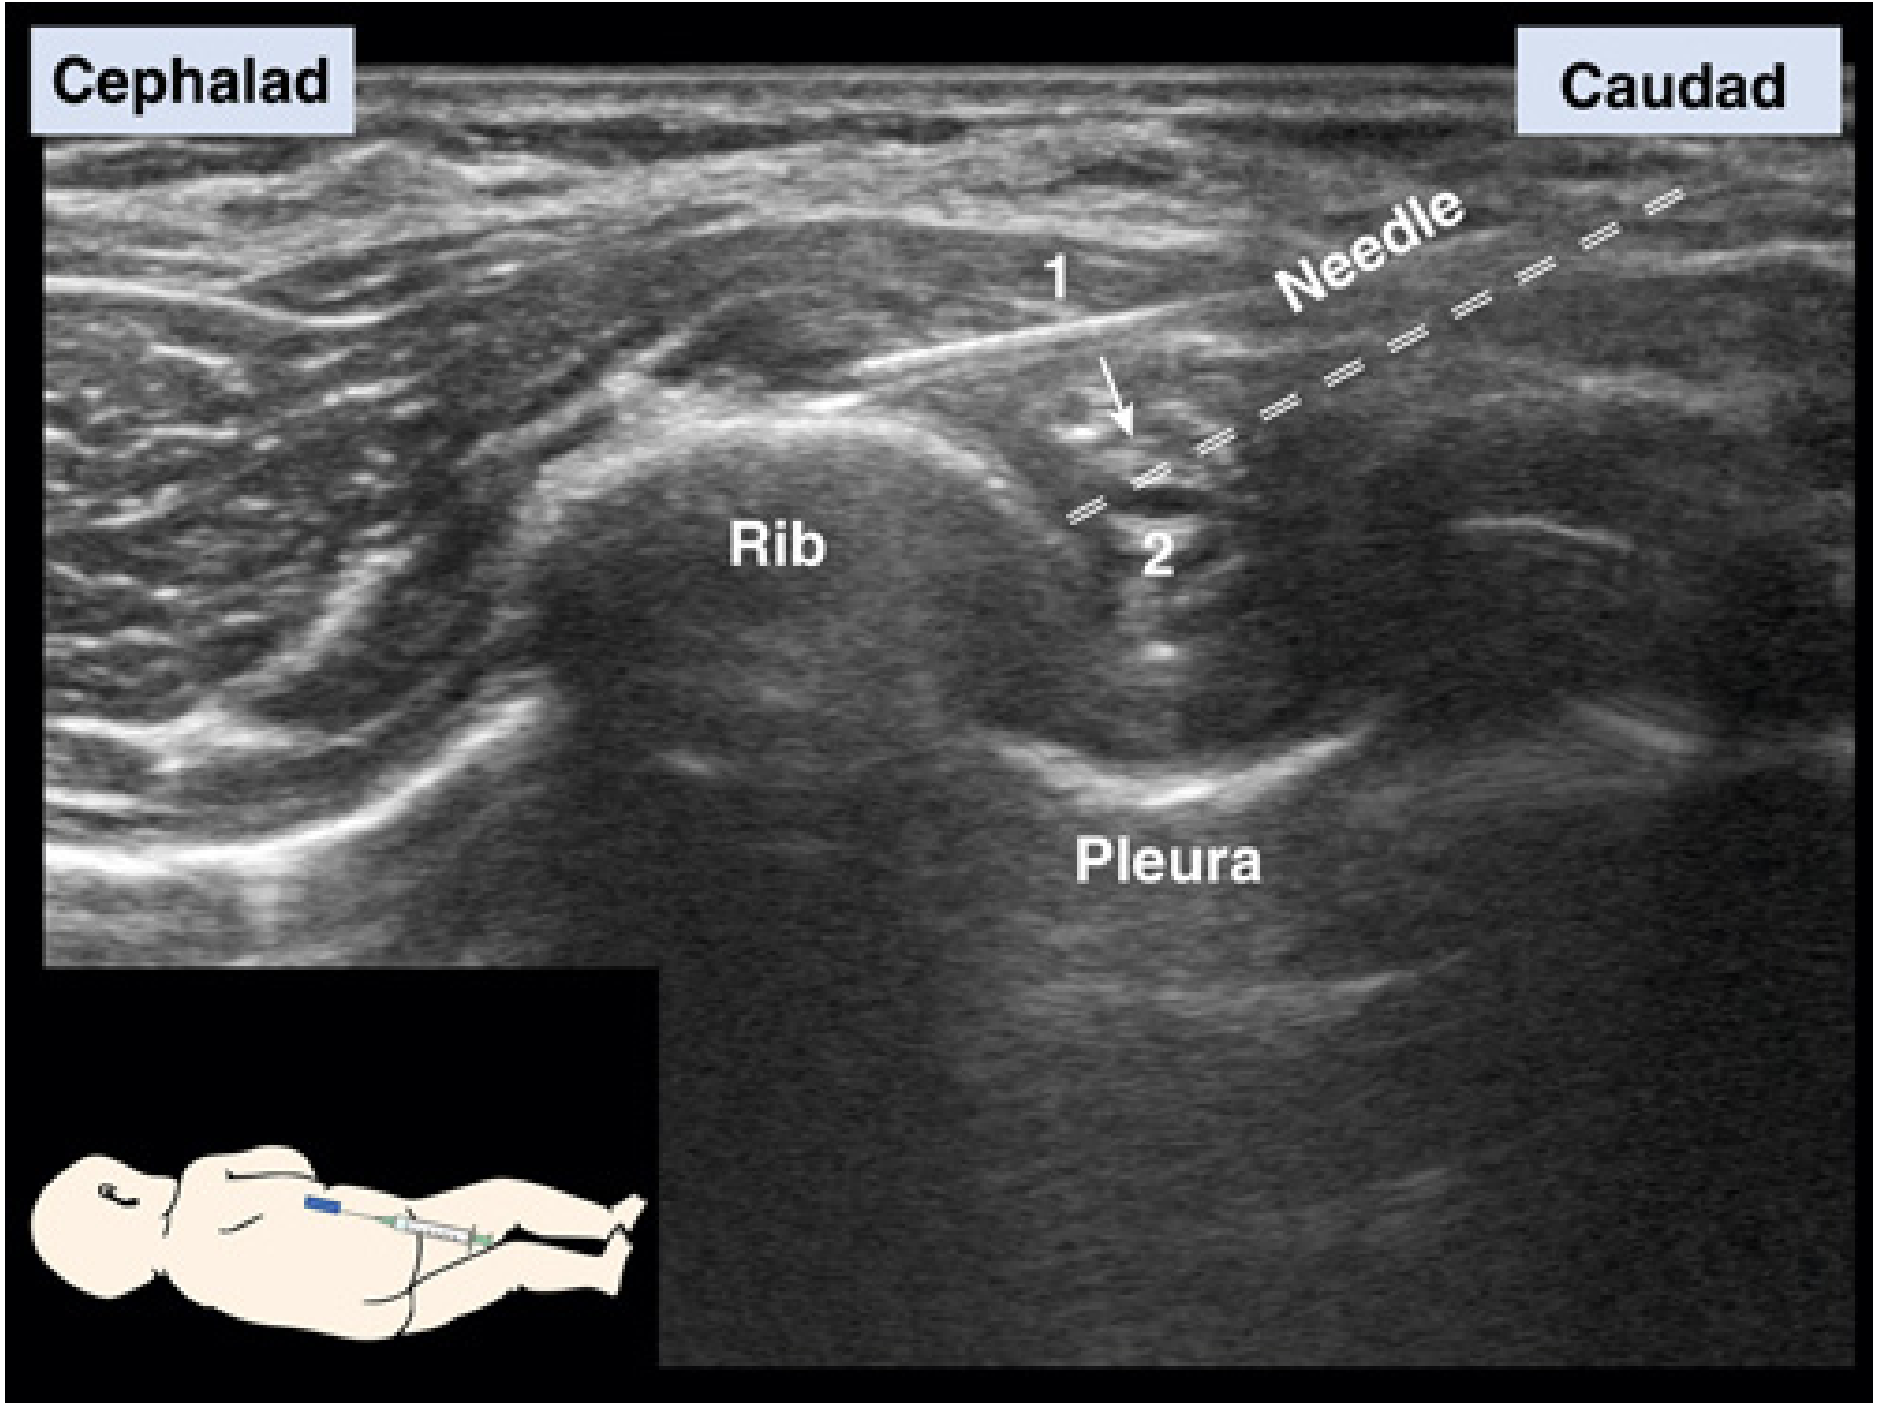

Technique

• Position: semi-prone at the midaxillary line — described as the safest approach in Miller's

• Needle: 22- or 20-gauge Tuohy needle (intradermal needles are explicitly stated as inappropriate)

• Guidance: In-plane ultrasound strongly preferred

Two-step needle manoeuvre:

1. Insert needle in-plane to contact rib

2. Redirect needle and walk off the rib caudally into the intercostal space

Intercostal nerve block — ultrasound-guided technique

Miller's Anesthesia, 10e, Fig. 74.32 — (1) Insert needle in-plane to contact rib. (2) Redirect needle caudally off the rib into the intercostal space.